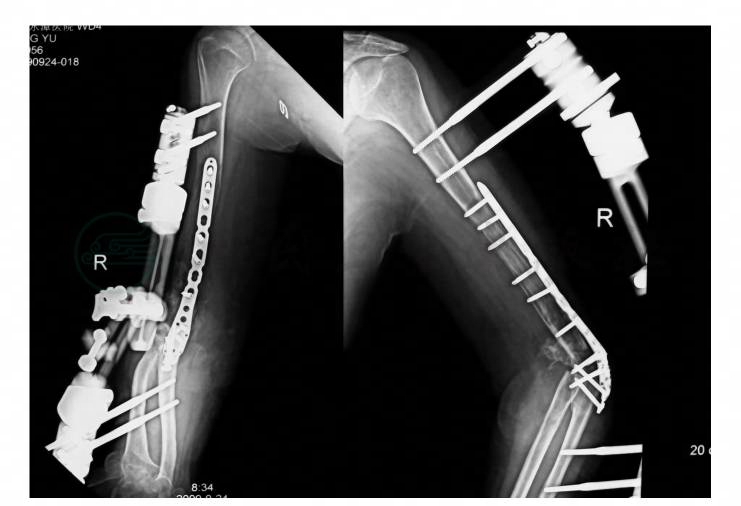

术后2个月X线片:肱骨干远段缺失约5cm,肱骨髁间骨折以2枚克氏针固定,单管状外固定架分别将位于肱骨和桡骨的2枚半针相连。肱骨远折端向后方移位明显。对位对线欠佳(图2)。

图2 伤后2个月X线片,右肱骨干远段缺失约5cm,肱骨远折端向后方移位明显。对位对线欠佳